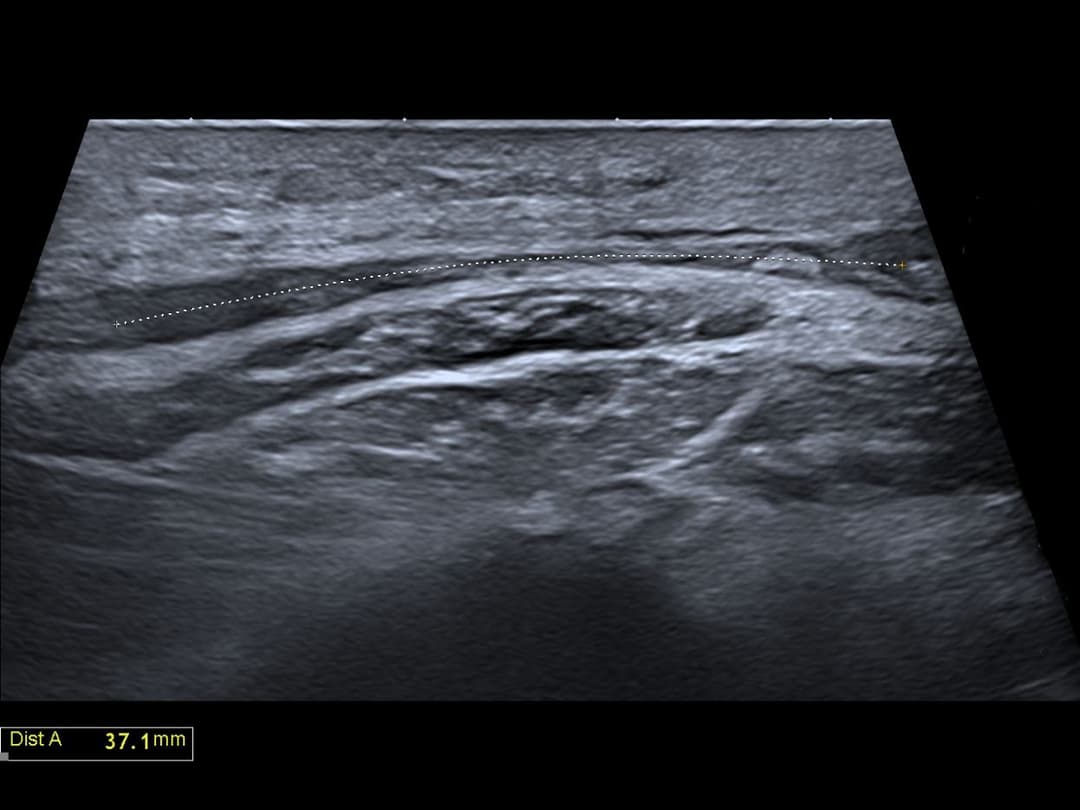

Echographie réalisé avant chirurgie pour marquage du nerf fibulaire commun.

Rupture complète de la continuité du nerf fibulaire commun juste après sa naissance du nerf sciatique, avec un écart interfragmentaire de 4 cm.

Ecart interfragmentaire de 4 cm